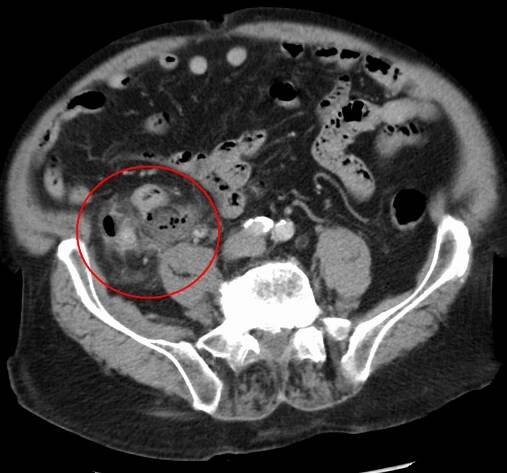

Peritonitida je zánět pobřišnice (serózní membrány, která obaluje část dutiny břišní a některé břišní orgány). Může být lokalizovaná nebo generalizovaná, obecně má akutní průběh a může být způsobena buď infekcí (často z ruptury dutého orgánu, například při poranění břicha), anebo neinfekčním procesem.

Zánět pobřišnice se odborně označuje jako peritonitida a řadíme ji mezi stavy označované jako náhlé příhody břišní. Jedná se o smrtelně nebezpečný stav, který je charakteristický průnikem bakterií do dutiny břišní.